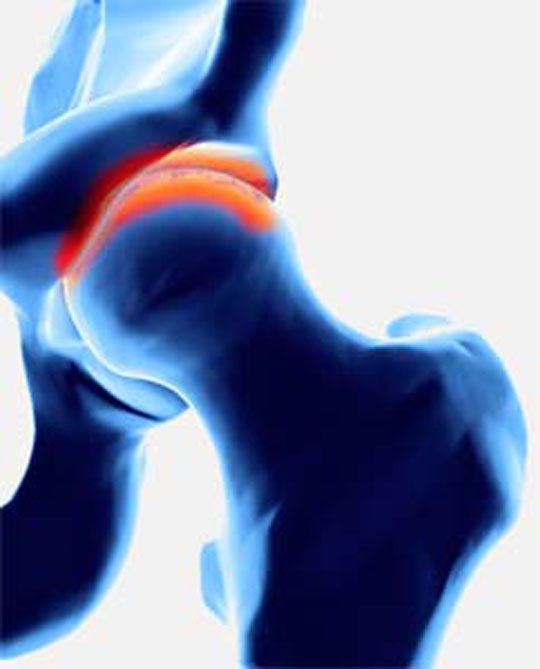

عللی که موجب بروز آرتروز مفصل ران ( آرتروز لگن ) می شوند در ابتدا موجب بروز تغییراتی در غضروف مفصلی می شوند. مهمترین تغییرات آرتروز مفصل لگن نازک شدن لایه غضروفی و تغییر جنس غضروف است. غضروف دیگر آن شادابی و خاصیت ارتجاعی و کلفتی کافی برای محافظت از مفصل را ندارد و باید برای درمان ارتروز لگن به پزشگ مراجعه نمایید. بدنبال تغییر در غضروف استخوان زیر آن سخت و محکم و کلفت می شود و گاهی در درون آن کیست های کوچکی بوجود می اید. بتدریج در لبه مفصل استخوان های اضافه ای رشد می کنند که به آن ها استئوفیت Osteophyte می گویند. کپسول مفصلی هم بتدریج ضخیم و کلفت شده و خاصیت ارتجاعی خود را از دست می دهد.

- بتدریج ممکن است بیماری آنقدر شدید شود که لایه غضروفی کاملا از بین رفته و در سطح مفصل، استخوان روی استخوان حرکت کند.

- در این وضعیت حرکت مفصل بطور طاقت فرسایی دردناک بوده و توانایی خم و راست شدن ران و یا چرخش ران بشدت کم می شود.

- در نهایت، روش های تصویر برداری مثل رادیوگرافی به تشخیص بیماری و درمان آرتروز لگن کمک می کند.

- در تصویر رادیوگرافی از مفصل، چون غضروف نازک شده است فاصله مفصلی یا فاصله بین دو استخوانی که مفصل را تشکیل داده اند و در حد چند میلیمتر است کاهش پیدا می کند و در کناره های استخوان های تشکیل دهنده مفصل استخوان اضافی دیده می شود.